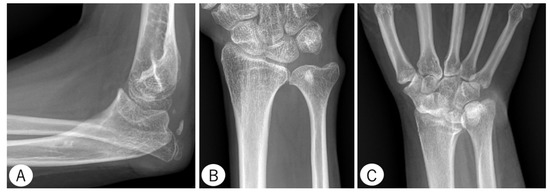

2.3.1. Elbow

- Anterior Coverage Index (ACI): defined as the ratio between the coronoid height (point A to B) and the minimal proximal ulna trochlear height (C to D).

- Trochlear Depth Index (TDI): defined as the ratio between the proximal ulna trochlear notch depth (F to G) and olecranon–coronoid distance (A to E).

- Proximal Ulnar Bow (PUB): defined as the angle between the ulnar diaphysis and olecranon.

- Radiographic Opening Angle (ROA): defined as the angle between lines from the deepest point of the trochlear notch to coronoid (A to G) and olecranon (G to E).

2.3.2. Wrist